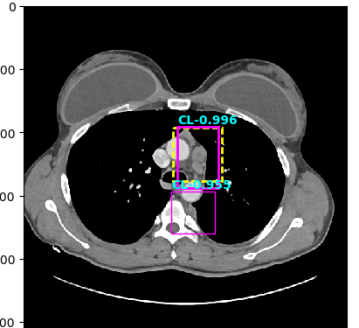

Figure 4: Six sample detection results are illustrated with the annotation lesion patches as yellow dashed boxes. The outputs from our proposed detection framework are shown in colored boxes with LiVer lesion (LV) in Red, Lung Nodule (LN) in Orange, ABdomen lesion (AB) in Green, Chest Lymph node (CL) in magenta and other MiXed lesions (MX) in blue. (a) Four lung lesions are all correctly detected; (b) Two lymph nodes in mediastinum is presented; (c) A Ground Glass Opacity (GGO) and a mass are detected in the lung; (d) An adrenal nodule; (e) Correct detections on both the small abdomen lymph node nearly aorta but also other metastases in liver and spleen; (f) Two liver metastasis are correctly detected. Three lung metastases are detected but erroneously classified as liver lesions .